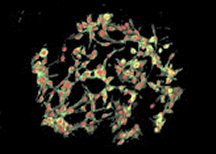

To see whether the heart has untapped potential to resuscitate itself, Anversa and his colleagues studied cardiac stem cells in 52 hearts that had been removed from people during heart transplantation or shortly after death from a heart attack or another cause. Such cells can give rise to heart muscle, arteries, and other tissue.

Cardiac stem cells can be prompted in that direction, however, according to tests on dogs that have had heart attacks. In the June 21 PNAS, Anversa and his team report injecting two growth-inducing proteins into the animals’ hearts. The treatment stimulated stem cells to migrate to dead areas of the dogs’ hearts and, once there, to regenerate muscle and arteries.